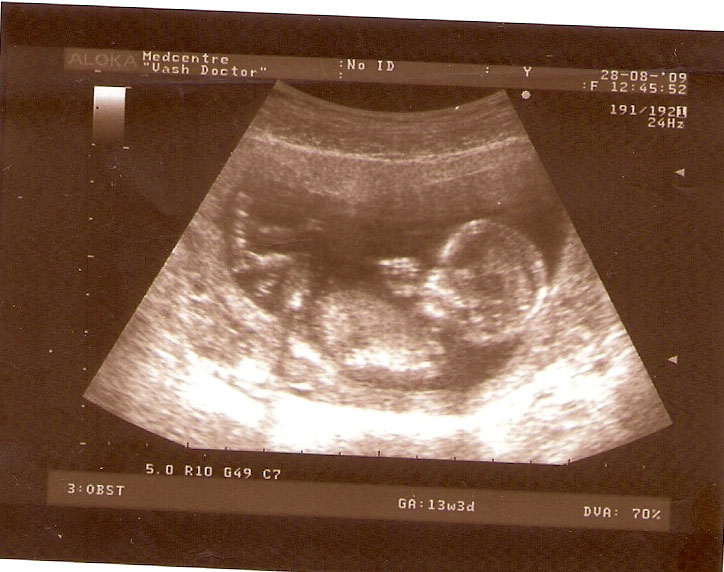

СЫН

| Вложения: |

2.jpg [ 110.14 КБ | Просмотров: 2625 ]

13 НЕД И 5 ДНЕЙ

3.jpg [ 96.81 КБ | Просмотров: 2623 ]

Nikisa писал(а): Foto prosto chudesnoe. A na kakom sroke uznali, chto sin.............. НА 13 НЕДЕЛЯХ.КАК РАЗ ВОТ В ЭТО узи, ОНО УМЕНЯ ВТОРОЕ БЫЛО. ЭТО КОНЕЧНО МАЛЕНЬКИЙ СРОК ДЛЯ ОПРЕДЕЛЕНИЯ ПОЛА. НО Я ПОПРОСИЛА ВРАЧА(ЭТО КТСТАТИВ РОССИИ БЫЛО) ХОТЯ БЫ ПРЕДПОЛОЖИТЬ. ЕЙ ВСЁ ТАКИ УДАЛОСЬ РАССМОТРЕТЬ.НУ ВООБЩЕМ ЧЕРЕЗ НЕСКОЛЬ ДНЕЙ ПОЙДУ К ВРАЧУ, УЖЕ АМЕРЕКАНСКОМУ И УЗНАЮ ТОЧНО. К ТОМУ ВРЕМЕНИ У МЕНЯ БУДЕТ СРОК 18 НЕДЕЛЬ. ХОТЕЛОСЬ БЫ ПОСМОТРЕТЬ НА ДРУГИЕ ФОТО НА ЭТОМ СРОКЕ ИЛИ БОЛЬШЕ. ТАК ЧТО ВЫКЛАДЫВАЙТЕ, ЕСЛИ НЕ ЖАЛКО!